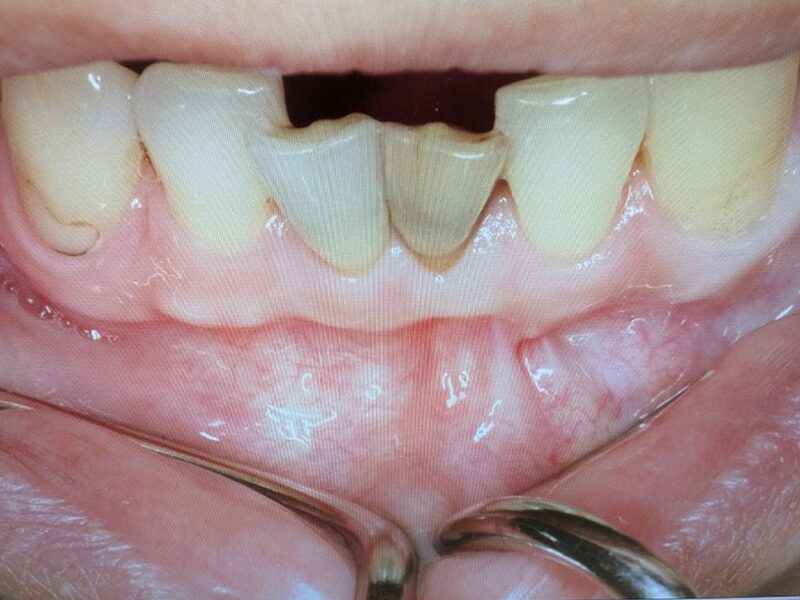

初診時は、下顎前歯部には根管治療が未実施で、頬側の歯肉に膿瘍を形成しておりました。患者様に状態を説明し、根管治療の後、外科的歯根端切除術および嚢胞摘出術を行う治療計画を説明しました。

前歯1番の左下の歯肉に膿瘍が形成されておりました。患者様には状態を説明して根管治療から開始しました。